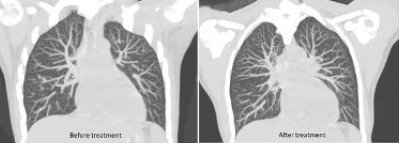

Pulmonary tuberculosis poses a diagnostic dilemma to clinicians especially in the absence of typical presentation. The hypersensitivity to tuberculosis infection in other parts of the body can lead to nondestructive, para-infectious arthritis. This is known as Poncet disease, one of the clinical syndromes of musculoskeletal tuberculosis. Herein, we report a case of smear-negative pulmonary tuberculosis presenting with atypical features. It started with multiple joint pain, followed by the presence of multiple tender nodular skin lesions over the bilateral shins and wrist. Subsequent investigations led to the diagnosis of smear-negative pulmonary tuberculosis. Joint pain and erythema nodosum disappeared soon after antituberculosis therapy, supporting the diagnosis of Poncet disease.